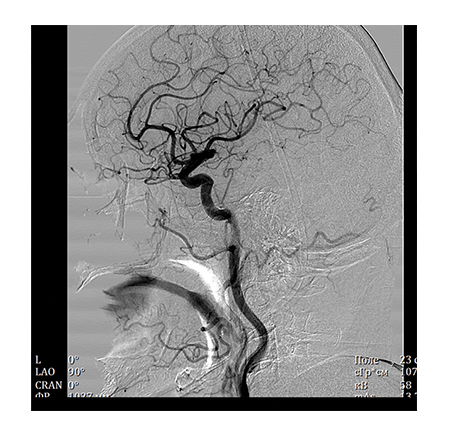

The X-ray angiography system developed by NIPK Electron Co. is a versatile system, which allows performing a wide range of diagnostic procedures:• Angiography of the brain and cervical vessels

A special value of the angiography system consists in high information content of the obtained image. A unique imaging system based on a flat panel detector with spatial resolution of 50 μm, which is superior to foreign analogs regarding its specifications, ensures high diagnostic imaging quality. The examinations allow not only to obtain information about the functional state of the vessels and reveal the signs of disorders but also help determine the accurate localization and seriousness of the revealed abnormality using special calculation packages.